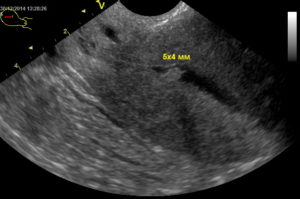

Полип – образование доброкачественной природы, которое состоит из увеличенного слоя эндометрия и находится в маточной полости или цервикальном канале. Новообразование может иметь разные размеры, варьирующиеся от 1 мм до 5-6 см, и «комплектацию»: вырост эндометрия может быть одиночным и диффузным. В последнем случае фиксируется множественные очаги наростов.

Размеры нароста в матке могут быть различными 1-30 мм. В среднем, не более 10 мм. Если полип ничем не беспокоить, он не растёт, но когда женщина часто делает аборты, беременеет, ей делают выскабливания, его рост может ускориться. После удаления полипа эндометрия доктор назначит вам болеутоляющие, возможно процедуры у гинеколога.

Подобные разрастания могут значительно отличаться по своим размерам: иногда это всего несколько миллиметров, а порою и более 10 см.